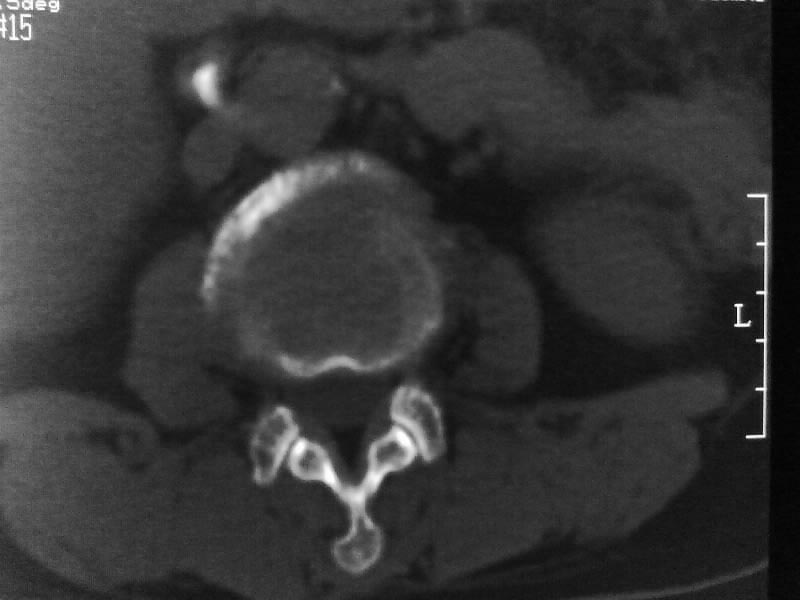

定位相示l2呈楔形改变(ct示陈旧性骨折改变,图像未传),l4.5椎体融合,以下是l4.5ct平扫.请各位看看,

考虑结核(有破坏、硬化及死骨)。

1、三四椎体结核,2、水平骶椎。

就是腰1压缩性骨折,腰3\\4椎体结核(融合),水平骶椎.

支持 l1椎体陈旧性压缩性骨折;l3、4椎体结核(融合);水平骶椎。